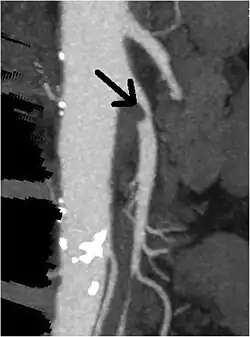

CT angiogram demonstrating stenosis of the superior mesenteric artery. | |

Abdominal angina is diagnosed by identifying stenosis with imaging.[10] Since the symptoms of abdominal angina overlap with various other disorders, other causes of symptoms are ruled out as a part of the diagnostic process. Gastric ulcers, abdominal aortic aneurysms, and gastrointestinal cancers can have similar symptoms and can be ruled out by esophagogastroduodenoscopy, CT scans, or MR angiogram. Other differential diagnoses include GERD, dietary or food sensitivities, constipation, pancreatitis, abdominal abscess, appendicitis, irritable bowel syndrome, gastroenteritis, hepatitis, and inflammation of the gastrointestinal system.[11] Duplex ultrasound, MR angiography, angiography, and computed tomography angiography can be used to help confirm the diagnosis of abdominal angina.[3] Duplex ultrasound may be used to screen for abdominal angina but is not ideal for visualizing stenosis. Angiography, MR angiography, or CT angiography can be used to further visualize the celiac and mesenteric arteries.[12]